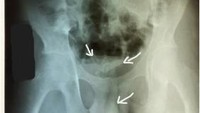

Seorang remaja di Sri Lanka harus menjalani operasi lantaran ada kabel ‘nyangkut’ di penisnya. Kabel tersebut diketahui sudah berada di dalam alat kelaminnya selama beberapa hari. Adapun kasusnya ini dipublikasikan di jurnal Psychiatry Research Case Reports (Foto: Psychiatry Research Case Reports).